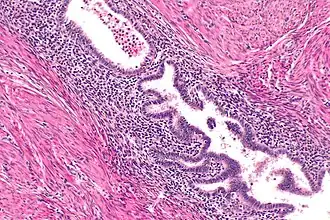

On microscopic examination, patterns of smooth muscle and endometrial tissue must be assessed with care to differentiate adenomyomas from masses of similar appearances, such as endometriosis containing smooth muscle and leiomyomas containing endometriosis.[3]